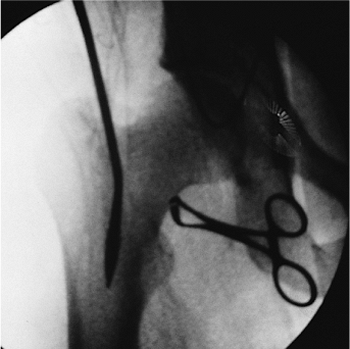

Figures 21.26. A,B.

Fracture reduction with crutch. A combination of maneuvers can be used to reduce the fracture in the sagittal plane. A crutch is often needed to support the distal fragment, which is pulled toward the floor by the two heads of the gastrocnemius muscle. The proximal fragment is pulled anteriorly by the hip flexors. Manual pressure applied on the anterior thigh may assist with reduction. Radiographic conformation of the crutch helps ensure fracture reduction and allows passage of the bead-tipped guide wire. |